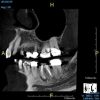

(8.) An original finding of a small lesion on the mesial root of tooth No. 30 was not accompanied by any outward symptoms; therefore, the patient delayed pursuing treatment. When a follow-up CBCT scan was acquired 6 years later, the easy-to-visualize increase in the dimensions of the lesion motivated the patient to elect a treatment plan.

Figure 8

(9.) An original finding of a small lesion on the mesial root of tooth No. 30 was not accompanied by any outward symptoms; therefore, the patient delayed pursuing treatment. When a follow-up CBCT scan was acquired 6 years later, the easy-to-visualize increase in the dimensions of the lesion motivated the patient to elect a treatment plan.

Figure 9

(10.) Tooth No. 31 in this 14-year-old patient does not exhibit caries. It is a “ghost tooth.” The lack of a periapical pathosis, the location of the tooth relative to the inferior alveolar nerve, and the development of tooth No. 32 are all visible in the CBCT image. These factors will aid the clinicians in developing a treatment plan to deal with this unusual internal resorption case.

Figure 10

Identifying the shape and location of the roots of teeth to be removed is critical to performing safe exodontia. Some clinicians virtually deconstruct teeth using CBCT images prior to actually sectioning and removing them. Being able to recognize pathoses and differentiate affected structures from normal structures is key in deciding what the treatment should be and when that treatment should be initiated (Figure 8 through Figure 10). The arena of the oral surgeon is larger than that of many general practitioners, involving the sinuses and condyles and other considerations in and around the entire mandible and maxilla. Certain fractures and other conditions that some general practitioners feel uncomfortable treating are often referred for evaluation and treatment by an oral surgeon. Because of this, oral surgeons require the most accurate and complete diagnostic information available. The American Academy of Oral and Maxillofacial Radiology recommends that "cross-sectional imaging be used for the assessment of all dental implant sites" and has stated that "CBCT is the imaging method of choice for gaining this information."18